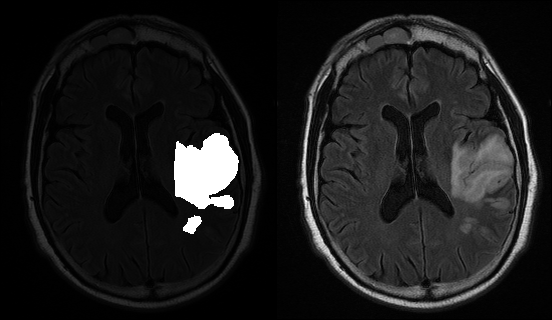

In short, brain lesions are abnormal tissue in/on brain tissue. We have refined a program (using the pix2pix tensorflow library) that will highlight brain lesions given a png image of a brain. This program will help automate the tedious task of manually highlighting brain lesions, and strives to perform just as well as a human operator.

The left side of this picture is an example of what we want to output, given the image on the right side.